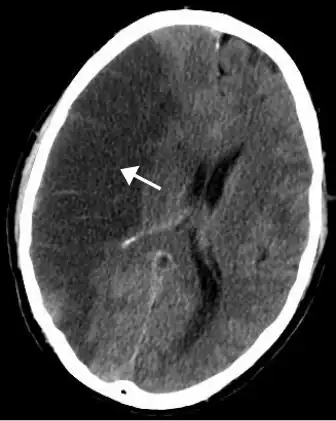

A radiological image of a stroke of the middle cerebral artery

A stroke of the middle cerebral artery can cause post-stroke depression